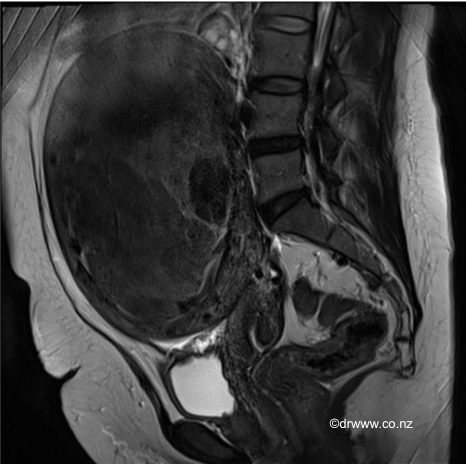

Fibroids may be diagnosed at the time of a pelvic examination, such as a Pap smear. Alternatively, the fibroid may be imaged by ultrasound, CT or MRI. MRI can be beneficial in assessing the location and size of individual fibroids

MRI image of a large 15cm fibroid that was managed with a Laparoscopic Myomectomy